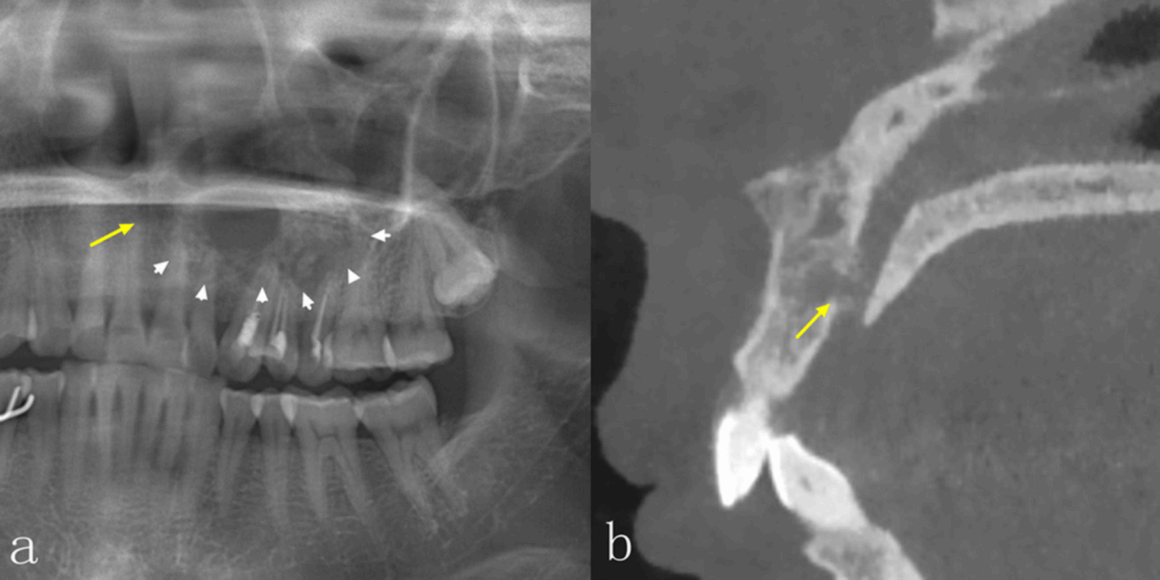

La radiografía panorámica (PAN) y la tomografía computarizada de haz cónico (TCCB) son dos modalidades radiográficas utilizadas en el diagnóstico, la planificación del tratamiento y el manejo de las enfermedades orales y maxilofaciales. No solo muestran las características de las lesiones en las imágenes, sino que también guían a los médicos para que realicen los diagnósticos más adecuados, así como los planes de tratamiento posteriores, y para supervisar la curación y/o la recurrencia de la enfermedad durante el seguimiento. La PAN, como técnica de imagen más común, puede proporcionar una visión general de las mandíbulas y la dentición, pero las estructuras anatómicas y las lesiones en las mandíbulas anteriores no están bien definidas debido a la superposición de las vértebras cervicales. Además, la calidad de la imagen de la PAN puede verse influenciada por la superposición de las estructuras anatómicas circundantes, las sombras de aire, las imágenes fantasmas y la sensibilidad a los errores de posicionamiento del paciente. Estos errores también darán lugar a una distorsión de la imagen y a un aumento desigual en las dimensiones horizontal y vertical. La CBCT, que se ha introducido ampliamente en la imagenología maxilofacial desde finales de la década de 1990, tiene ventajas sobre la PAN bidimensional PAN bidimensional, debido a su naturaleza tridimensional. La CBCT no solo muestra las estructuras anatómicas y las lesiones en los planos axial, coronal y sagital, sino que también permite realizar una variedad de efectos de posprocesamiento.

Es bien sabido que la TCCB presenta numerosas ventajas en el diagnóstico de enfermedades orales y maxilofaciales. En comparación con la PAN, la TCCB puede proporcionar más información para ayudar a los odontólogos a realizar diagnósticos, diseñar planes de tratamiento y supervisar los seguimientos postoperatorios. Actualmente, hay una escasez de estudios que se centren en las diferencias de las características radiográficas entre la PAN y la TCCB para obtener imágenes de las lesiones intraóseas de la mandíbula mediante un método cuantitativo. El estudio más reciente, con 31 casos incluidos, mostró que, aunque había diferencias en el aspecto radiográfico de las lesiones intraóseas en la PAN y la TCCB, la TCCB no ayudaba a mejorar la precisión del diagnóstico. Los autores concluyeron que el bajo número de casos de su estudio era una limitación. Por lo tanto, los objetivos de este estudio, que utilizó un mayor número de lesiones, fueron: investigar las diferencias en las características de imagen de las lesiones intraóseas de la mandíbula entre PAN y TCCB; y determinar con mayor precisión la eficacia diagnóstica de las dos modalidades radiográficas en la evaluación de las lesiones intraóseas de la mandíbula.

Las diferencias significativas en el aspecto radiográfico de las lesiones intraóseas entre la PAN y la TCCB se observaron en la integridad de los bordes corticales, la expansión de los límites anatómicos circundantes, el adelgazamiento cortical, la destrucción cortical y la reabsorción radicular, especialmente en las regiones anteriores de ambos maxilares y en el maxilar superior. La TCCB también mejoró la precisión diagnóstica, especialmente en las lesiones del maxilar superior. Los radiólogos se mostraron más seguros al utilizar TCCB en comparación con PAN. Estos hallazgos podrían utilizarse en el desarrollo de directrices para la obtención de imágenes de patologías intraóseas en los maxilares.